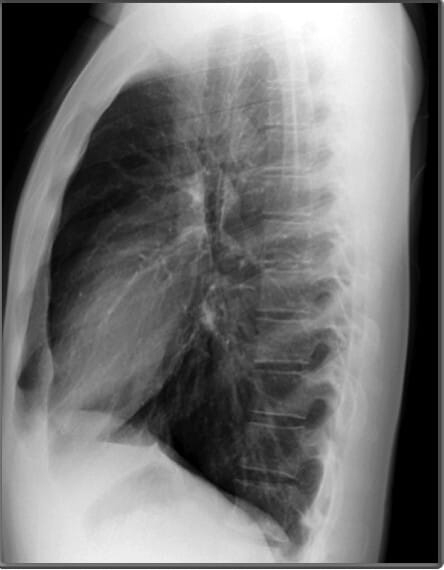

Lateral View of Chest X-ray

측면 영상은 폐, 심장 및 척추의 깊이를 평가하는 데 유용합니다.

| 흉골 (Sternum) |

| ✅ 측면 영상에서 길게 보이며, 정상적으로는 매끄럽고 연속적인 윤곽을 보여야 합니다. 골절이 있는 경우 불연속적인 선이 관찰될 수 있습니다. |

| 우심실 (Right Ventricle) |

| ✅ 심장의 전방 부분을 차지하며, 비대해지면 폐고혈압을 고려할 수 있습니다. |

| 좌심방 (Left Atrium) |

| ✅ 좌심방은 측면 영상에서 심장 후방에 위치하며, 기관(trachea) 바로 앞쪽에 위치합니다. 좌심방이 확장되면 기관이 뒤로 밀리는 소견이 나타날 수 있습니다. |

| 좌심실 (Left Ventricle) |

| ✅ 좌심실은 심장의 가장 하부와 후방을 차지하며, 비대해지면 좌측 횡격막과의 경계가 불명확해질 수 있습니다. |

| 척추체 (Vertebral Bodies) |

| ✅ 척추체는 정상적으로 크기와 모양이 균일해야 하며, 압박 골절이나 골 용해 소견이 있으면 병적 상태를 고려해야 합니다. |

하늘색이 Vertebral bodies, 파란색 (코발트 블루)가 Pedicles| 기관 (Trachea) |

| ✅ 흉부 중앙에서 공기가 가득 찬 검은 색의 관 형태로 보이며, 정상적으로는 앞쪽으로 약간 기울어져 있습니다. 협착되거나 편위된 경우 기도 병변을 의심할 수 있습니다. |

| 늑골횡격막각 (Costophrenic Angle) |

| ✅ 늑골과 횡격막이 만나는 각도로, 정상적으로 뚜렷하고 예리하게 보여야 합니다. 둔해지거나 소실되면 흉수(pleural effusion) 가능성을 시사합니다. |